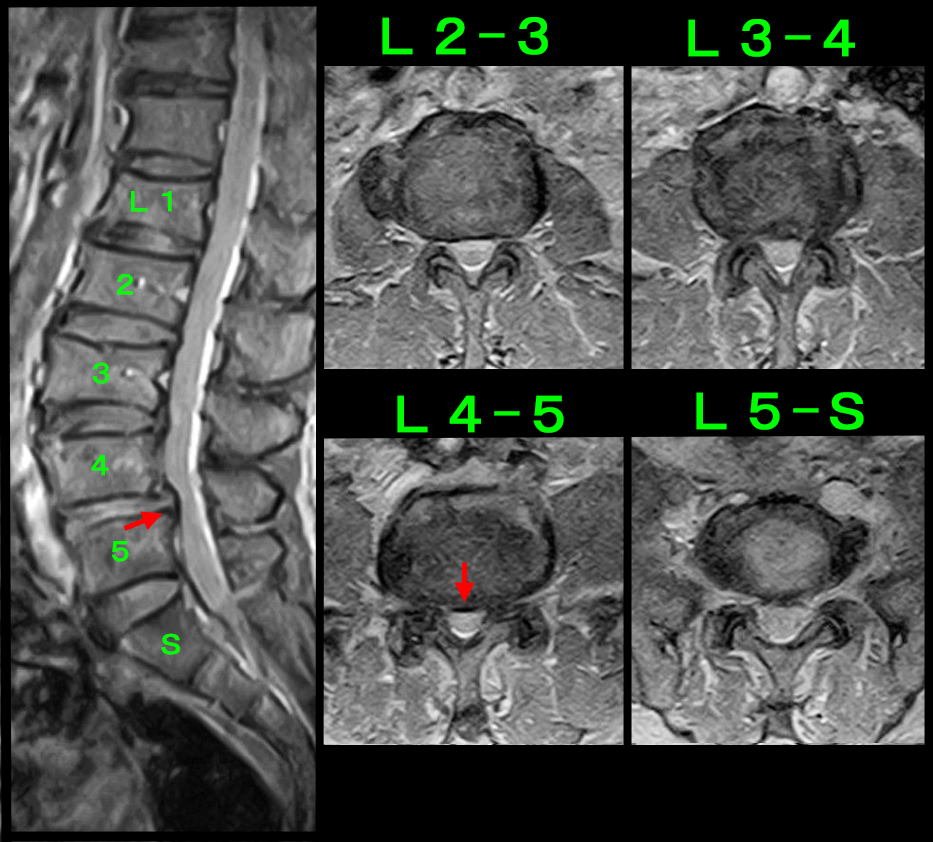

腰に起因する左坐骨神経痛と判断し、腰椎MRI検査ではL4-5の脊髄の圧迫が平成25年4月の時より悪化していました。やはり左L5神経根ブロックを施行して、左のふくらはぎ痛は軽減し、翌日の法事も問題がなかったと後日教えてもらいました。

2016.4.1.c.jpg2016.RB2.jpg